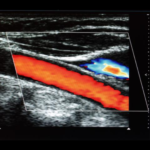

- Doppler de pene